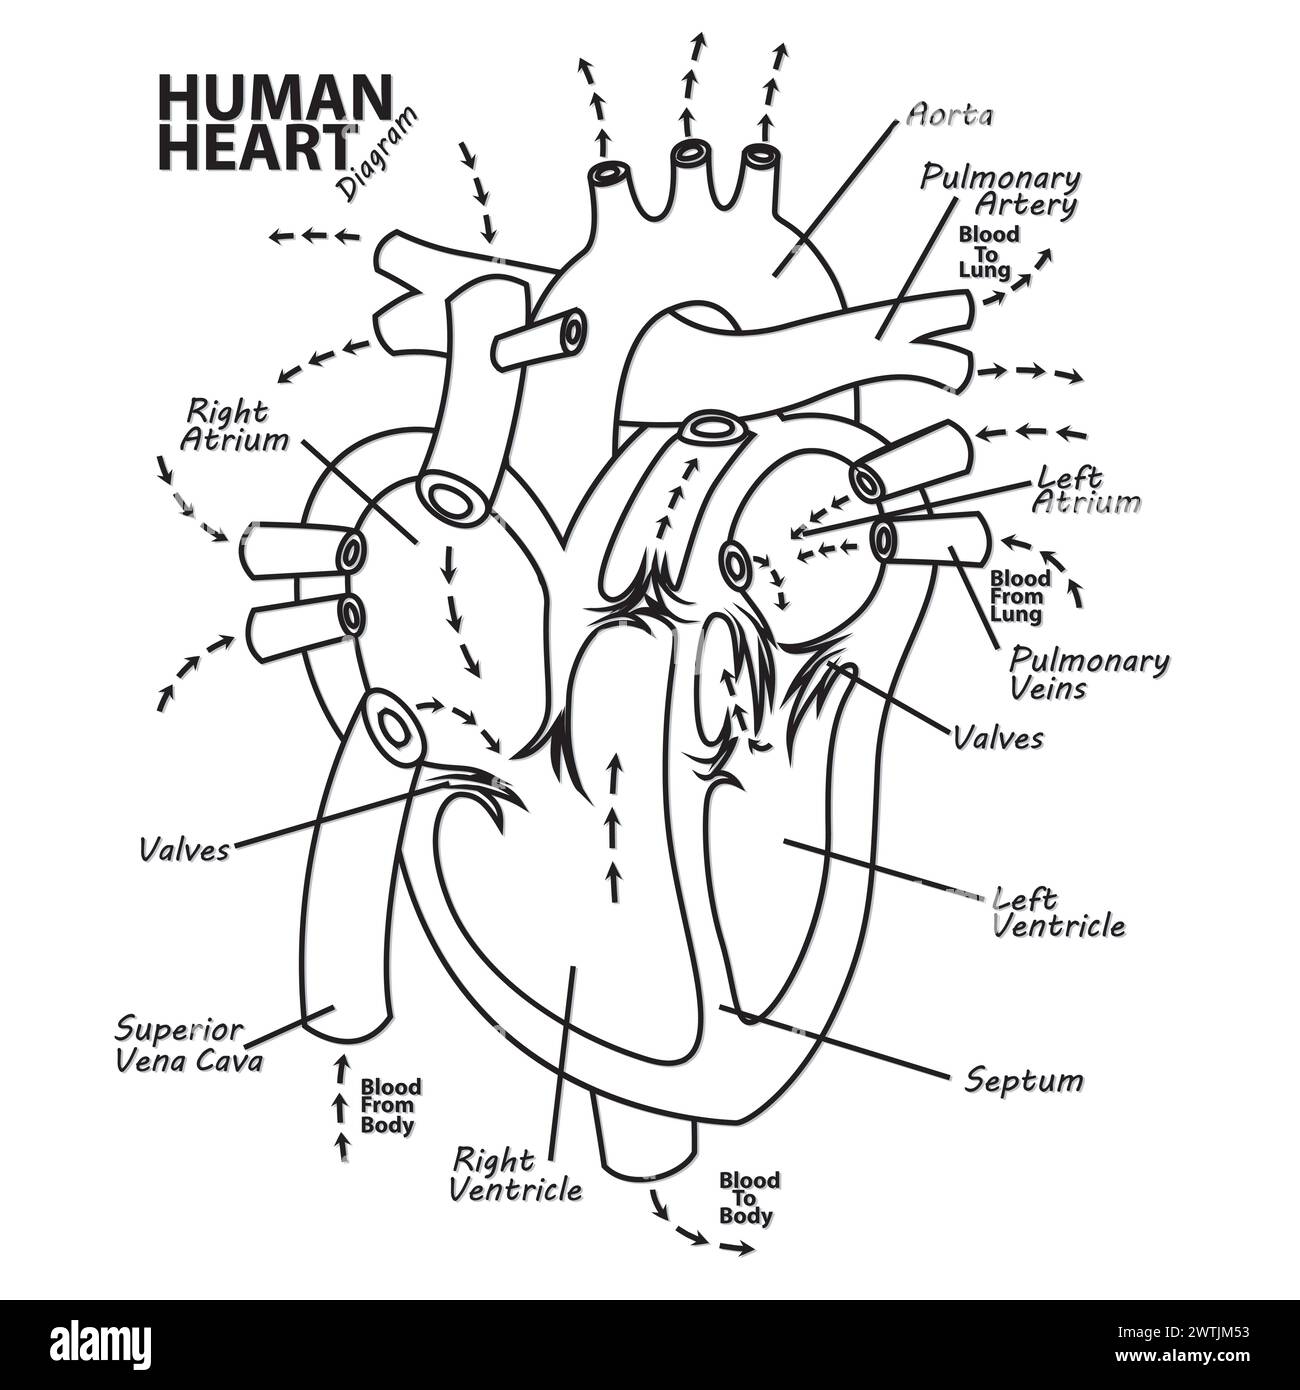

Anatomy of the human heart. Cross sectional diagram of the heart with main parts labeled. Human heart diagram Vector illustration. Educational diagram Stock Vectorhttps://www.alamy.com/image-license-details/?v=1https://www.alamy.com/anatomy-of-the-human-heart-cross-sectional-diagram-of-the-heart-with-main-parts-labeled-human-heart-diagram-vector-illustration-educational-diagram-image551609872.html

Anatomy of the human heart. Cross sectional diagram of the heart with main parts labeled. Human heart diagram Vector illustration. Educational diagram Stock Vectorhttps://www.alamy.com/image-license-details/?v=1https://www.alamy.com/anatomy-of-the-human-heart-cross-sectional-diagram-of-the-heart-with-main-parts-labeled-human-heart-diagram-vector-illustration-educational-diagram-image551609872.htmlRF2R1C00G–Anatomy of the human heart. Cross sectional diagram of the heart with main parts labeled. Human heart diagram Vector illustration. Educational diagram